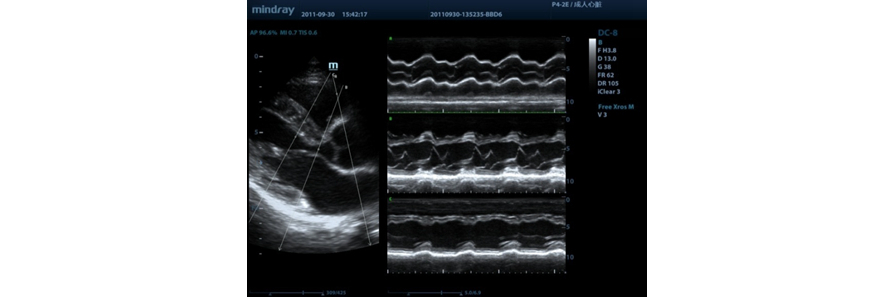

Free Xros M?

Modo M anatómico permite realizar las observaciones y medidas anatómicamente precisas independientemente de la orientación. Provee mejores imágenes a través de la visualización simultánea de hasta 3 líneas M.